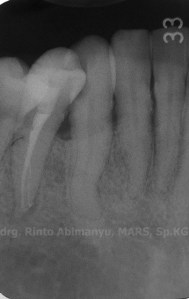

Radiografis gigi 43 selesai perawatan

Alhamdulillaaaah… saluran yang sedikit meliuk itu berhasil diisi dengan baik… 🙂

Pada kasus ini yang bisa dijadikan catatan adalah : dalam menghadapi saluran akar yang agak ada belok2 usahakan sabar dalam penjajakan awal, pastikan pada saat penjajakan tersebut file yang digunakan sudah dapat keluar masuk tanpa hambatan sehingga akan memudahkan file rotary yang kita gunakan untuk meluncur di saluran akar itu…